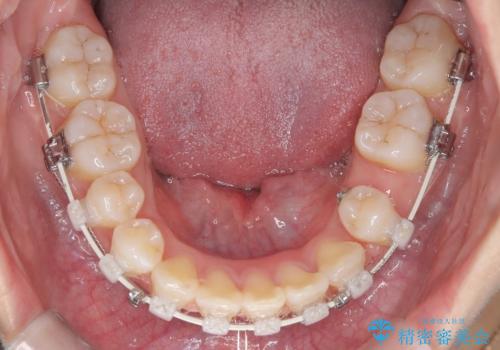

- 患者様は下顎の前歯が3本しかないという特異な歯列を持ち、噛み合わせのバランスが崩れていました。上下の歯の本数が通常と異なるため、抜歯部位の選定が重要となるケースでした。診査の結果、歯の位置や咬合のバランスを考慮し、上顎の両側小臼歯2本と左下の小臼歯1本を抜歯することで、上下の噛み合わせを整える方針としました。矯正装置は、**目立ちにくいハーフリンガル(上顎は裏側矯正・下顎は表側矯正)**を採用しました。

まず、計画通りに抜歯を行い、歯列のスペースを確保しました。上顎は裏側矯正(リンガル)で目立たないように配慮しながら歯を後方へ移動し、下顎は表側矯正を使用して、3本の前歯の位置関係を調整。上下の歯の噛み合わせを細かくコントロールしながら、全体のバランスを整えました。治療後は「歯並びがきれいになり、噛み合わせもしっかり合うようになった」と患者様にも満足していただけました。